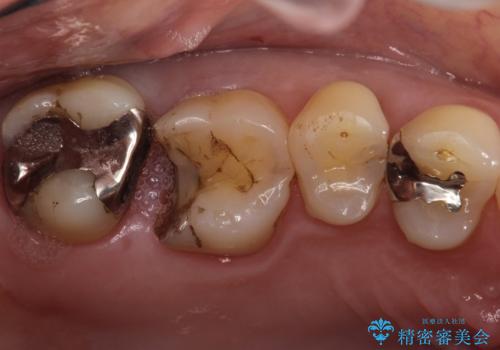

- 銀歯が外れて、中が虫歯になっているところがありました。

虫歯を取り除き、ゴールドインレーを装着する治療計画としました。

ゴールドは目立つという欠点がありますが、適合が良く、割れることもないため、長期的に安定した治療法となります。